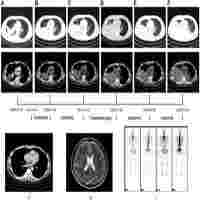

ALK gene rearrangement in NSCLC by NGS: an EQA case report

| Subject Keyword | Journal: Pathology Medical Laboratory Technology Next Generation Sequencing Gene Rearrangement Immunohistochemistry |